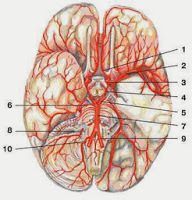

Внутренняя сонная артерия вместе с ее ветвями (передней мозговой и задней соединительной артериями), анастомозирующими с одноименными артериями противоположной стороны, образуют артериальный (виллизиев) круг большого мозга (circulus arteriosus cerebri), (рис. 397).

Рис. 397.Передняя и задняя мозговые артерии и артериальный круг большого мозга. Вид снизу. Передняя часть левой височной доли и левое полушарие мозжечка удалены.

1 — передние мозговые артерии, 2 — передняя соединительная артерия, 3 — внутренняя сонная артерия, 4 — средняя мозговая артерия, 5 — задняя соединительная артерия, 6 — верхняя мозжечковая артерия, 7 — задняя мозговая артерия, 8 — базилярная (основная) артерия, 9 — позвоночная артерия, 10 — передняя спинномозговая артерия, 11 — нижняя задняя мозжечковая артерия, 12 — нижняя передняя мозжечковая артерия, 13 — тройничный нерв, 14 — отводящий нерв, 15 — средняя мозжечковая ножка, 16 — лицевой нерв, 17 — преддверно-улитковый нерв, 18 — языкоглоточный нерв, 19 — блуждающий нерв, 20 — мост мозга, 21 — глазодвигательный нерв, 22 — зрительный тракт, 23 — зрительный перекрест, 24 — обонятельный тракт, 25 — обонятельная луковица.

Сосудистые мозговые бассейны Как для магистиральных мозговых артерий, так и для артерий, питающих центральные отделы мозга [лентикуло-стриарные артерии, возвратные артерии Гюбнера (т.н. средняя стриарная артерия) и др.] характерна значительная вариабельность как в зонах их кровоснабжения, так и в местах их отхождения от ПМА и СМА.

- Виллизиев круг

Символ «⇒» обозначает область, кровоснабжаемую указанной артерией. Ангиографические диаграммы описываемых сосудов см. Церебральная ангиография. Правильно сформированный Виллизиев круг имеется только в 18% случаев. Гипоплазия одной или обеих ЗСА встречается в 22-32% случаев; сегмент А1 может быть гипоплазирован или отсутствует в 25% случаев. В 15-35% случаев одна ЗМА получает кровоснабжение через ЗСА из ВСА, а не из ВБС, а в 2% случаев обе ЗМА кровоснабжаются через ЗСА (фетальное кровоснабжеиие).

Рис. 3-10. Виллизиев круг (вид с основания мозга)